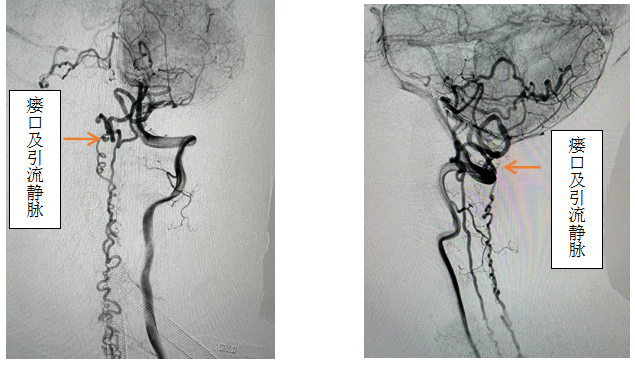

,效果欠佳。入院时已经行走困难,行颈椎核磁见颈椎蛛网膜下腔异常信号影,请神经外科会诊后考虑硬脊膜动静脉瘘可能性大,转入神外后立即由李帅主治医师行全脊髓血管造影,见“左侧椎动脉V4段发出脑膜支,其远端分支供血形成硬脊膜动静脉瘘,瘘口位于枕骨大孔区,经延髓背侧及腹侧向下引流至胸2椎体节段”。缪星宇主任主持全科病例讨论,讨论考虑患者经脊髓血管造影后诊断明确,手术指征明确,可行硬脊膜动静脉瘘介入栓塞术或开颅阻断术。术中可采取“高压锅”技术防止栓塞胶的返流,降低微导管的到位要求,降低返流空间的要求,使得返流空间安全可控,缩短注胶时间,增加胶的弥散效率,从一定程度上提高栓塞比例,增加患者的安全性。如介入微导管到位困难,可以考虑开颅阻断瘘口,但瘘口位置距离呼吸中枢延髓较近、术中风险大且术后患者恢复时间长。科室讨论后决定利用黑料网先进的复合手术室,首先采用第一方案“高压锅”技术使胶完全封堵瘘口,若不能到位或完全封堵,则采用第二方案,转为开颅阻断瘘口。手术当日,由黄卫东主任医师和李帅主治医师操作,第一根栓塞微导管顺利到达瘘口,第二根微导管接近栓塞微导管后使用弹簧圈顺利形成高压锅塞子,经第一根微导管注入栓塞胶,射线透视下见栓塞胶按预期流向瘘口,栓塞满意后造影示瘘口及引流静脉均未见显影,手术成功。术后患者恢复良好,第二天即下床活动,下肢活动明显恢复,5天后步行出院。